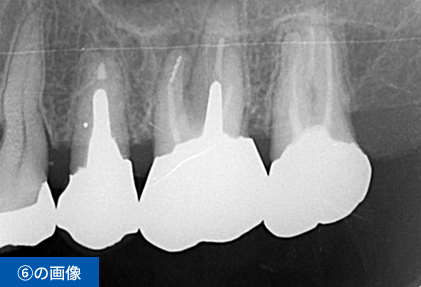

左下④56⑦番のブリッジの脱離にて来院(④⑦はブリッジの支台歯56は欠損)

| 費用 ※保険外診療 | 総額1,485,000円(税込) インプラント3本、手術2回、CGF、遊離歯肉移植、CT撮影、被せ物の型取り(印象)、被せ物(フルジルコニア)3本、投薬 |